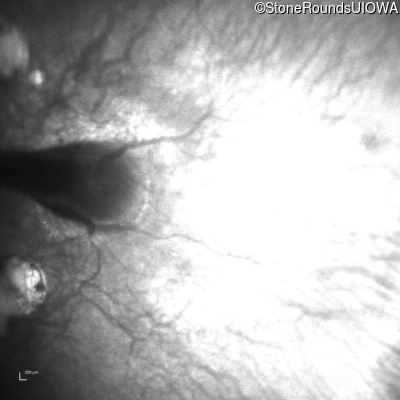

Infrared Fundus Photograph - Left - 20/250

Exemplar